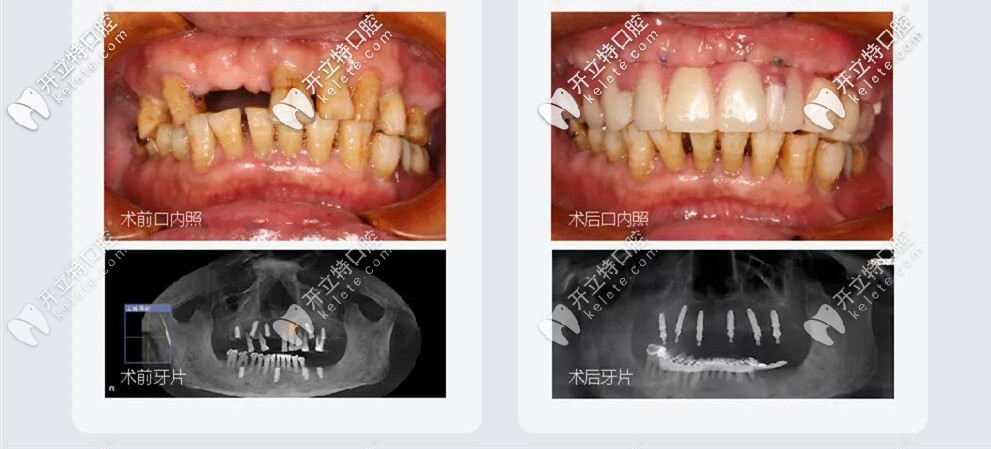

王叔叔已經(jīng)60多歲了,但是口內(nèi)牙齒松動(dòng),部分牙齒已經(jīng)缺失,牙齒縫隙大,牙槽骨萎縮,每天吃東西都比較困難;

All-on-6種植牙前后照

王叔叔的孩子們?yōu)榱俗约旱睦习帜馨蚕硗砟?,吃好喝好,在百般勸說下帶著王叔叔來到了成都極光口腔找劉東偉醫(yī)生做的種植牙;劉醫(yī)生結(jié)合顧客需求以及自己的經(jīng)驗(yàn),采取的方案是:拔除松動(dòng)的牙齒,用極光美式定制植牙All-on-6微創(chuàng)種植牙技術(shù);王叔叔當(dāng)天植牙,當(dāng)天戴牙;

微創(chuàng)種植牙治療前后對(duì)比圖

當(dāng)天做完種植牙,就恢復(fù)咀嚼功能啦,種完就回家了,不腫不痛也很輕松。